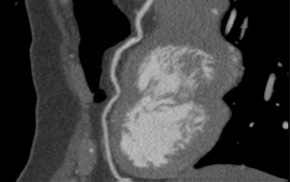

CT Coronary Angiography

3. Plaque characterization, quantification and progression

4. Functional assessment of anatomical stenosis

5. Downstream resource utilization

6. Appropriateness of use

CT Ventricular Function